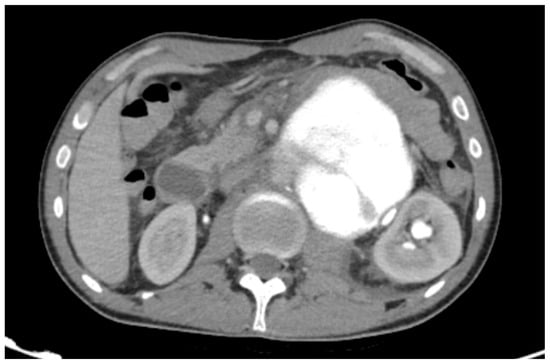

Managing Gallstone Ileus and Surgical Considerations in Resource-Limited Settings: A Case Series from the Amazon Jungle

Gallstone ileus is a rare but serious complication of gallstone disease, often requiring surgical intervention. While enterolithotomy remains the standard treatment, the role of additional biliary surgery, particularly subtotal cholecystectomy, remains controversial. This study examines the management of gallstone ileus in a rural [...] Read more.

Gallstone ileus is a rare but serious complication of gallstone disease, often requiring surgical intervention. While enterolithotomy remains the standard treatment, the role of additional biliary surgery, particularly subtotal cholecystectomy, remains controversial. This study examines the management of gallstone ileus in a rural setting, where limited surgical resources and access to specialized biliary interventions pose unique challenges. We present a case series of four patients diagnosed with gallstone ileus in a rural healthcare facility. All patients underwent initial enterolithotomy for bowel obstruction relief. Surgical outcomes, complications, and the necessity for a second intervention, including subtotal cholecystectomy, were evaluated. Ever patient had a successful recovery. Of the four cases, two patients underwent a subtotal cholecystectomy. No perioperative mortality was observed, but limited access to advanced imaging and specialized biliary surgery influenced clinical decision-making. The rural setting in which these series occurred comes with its unique challenges regarding resource management and technological demands. Full article

Show Figures

Figure 1